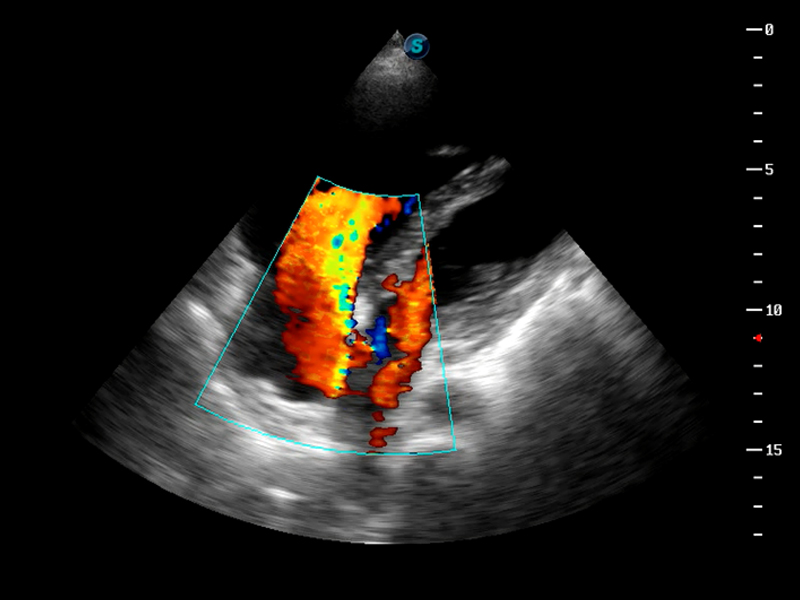

TDI组织多普勒成像

AutoC智能血流追踪